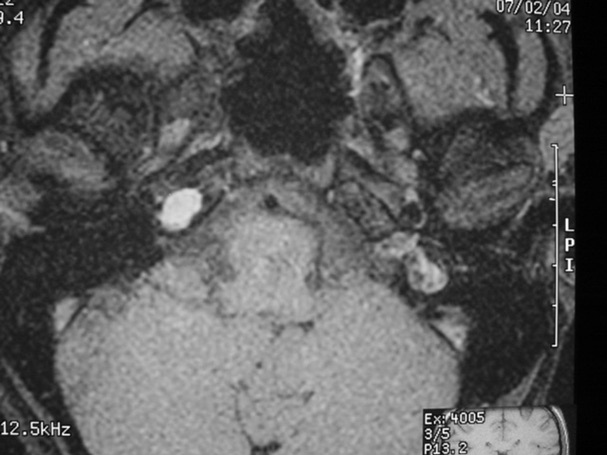

The petrous apex is a relatively inaccessible area that can occasionally harbor serious disease. Disease processes that usually cause symptoms are typically inflammatory or neoplastic in nature. Petrous apex lesions typically cause nonspecific symptoms such as headache, but as the lesion becomes more extensive, adjacent structures such as cranial nerves can become involved. A common early and specific sign of a petrous apex process is abducens palsy. Current imaging techniques can usually provide enough supplemental information to allow a focused plan of treatment. It is important to determine whether a petrous apex lesion can be observed or, if surgical treatment is required, whether a drainage or excision is required. There are various available surgical approaches to the petrous apex. The choice depends on the status of hearing function as well as the suspected pathology, which will dictate whether a drainage or excisional procedure is required.

- Summarize the types of pathology that can occur in the petrous apex, the imaging required, and proper interpretation of information so that a proper differential diagnosis can be formulated.